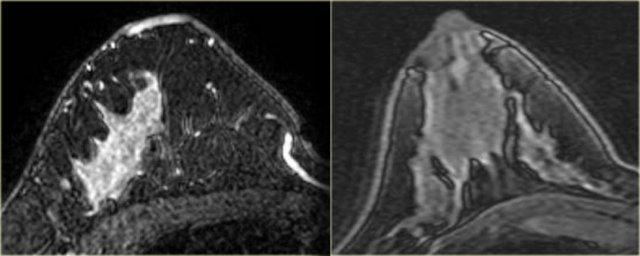

Bên trái là hai trường hợp.

Hình ảnh ngoài cùng bên trái là ung thư ống tuyến xâm lấn biểu hiện dưới dạng khối lớn ngấm thuốc không đồng nhất.

Kế bên là ví dụ về ung thư ống tuyến xâm lấn biểu hiện dưới dạng khối nhỏ hơn với ngấm thuốc dạng viền.